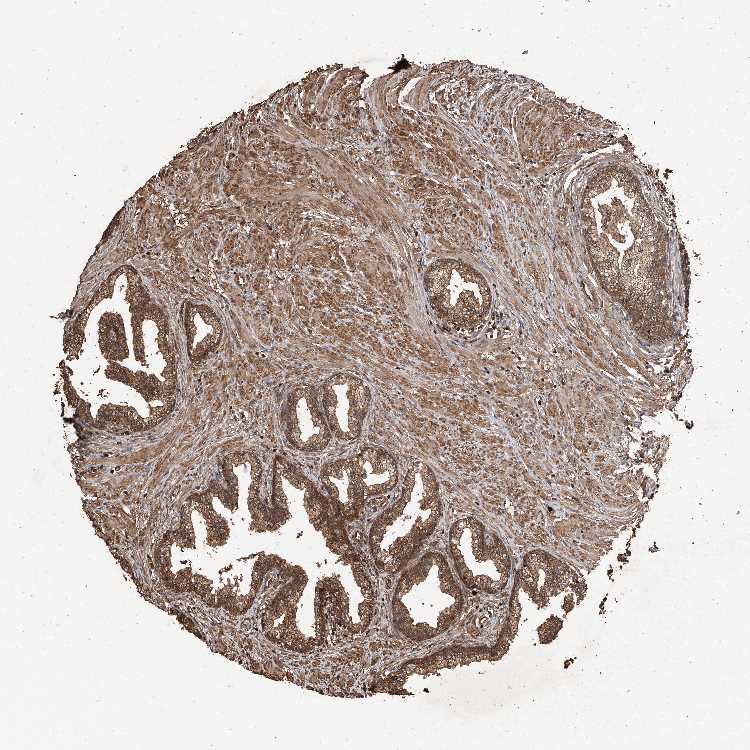

UCP2